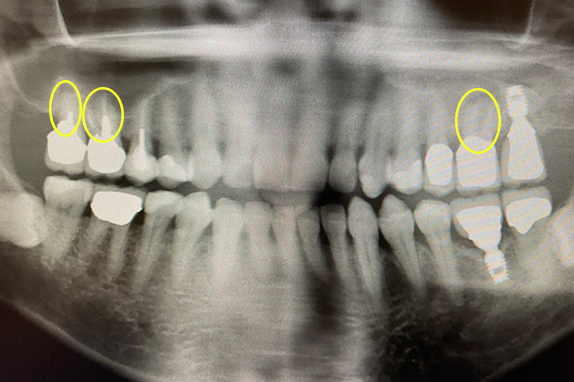

CASE 02 マイクロエンド(精密根管治療)+歯周基本治療

-

- 主訴

- 右も左も痛くて噛めない(60代女性)

-

- 回数期間

- 15回 約6ヶ月

-

- 治療法

- マイクロエンド(精密根管治療)+歯周基本治療

-

- 治療費用

- 約60万円(税抜)

右も左も痛くて噛めないという主訴で来院。マイクロエンドをし歯周基本治療で改善したケースです。

<リスク・副作用>

治療後は痛み、腫れ、痺れなどの副作用が生じる場合があります。症状が再発する可能性があります。